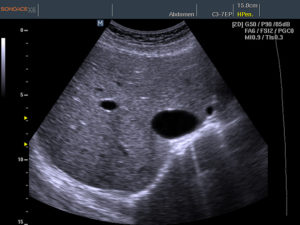

- ультразвуковое исследование;

Но более информативным методом диагностики является ультразвуковое исследование. Одним из важных диагностических признаков в этом случае являются диффузные изменения железы. Контуры органа при этом могут быть неровными, а ее размеры, как правило, находятся в пределах нормы.

Важный метод диагностики фиброза поджелудочной железы – ультразвуковое исследование органов брюшной полости (УЗИ брюшной полости). Определяется диффузное повышение эхогенности органа, структура неоднородная, размеры уменьшены; возможно выявление расширения вирсунгова протока.

Более информативна эндоскопическая ультросонография, которая позволяет выявить линейные тяжистые включения разной протяженности и формы, бугристость контуров, гиперэхогенность паренхимы. При проведении ЭРХПГ выявляются изменения протокового аппарата, вызванные образованием рубцов.